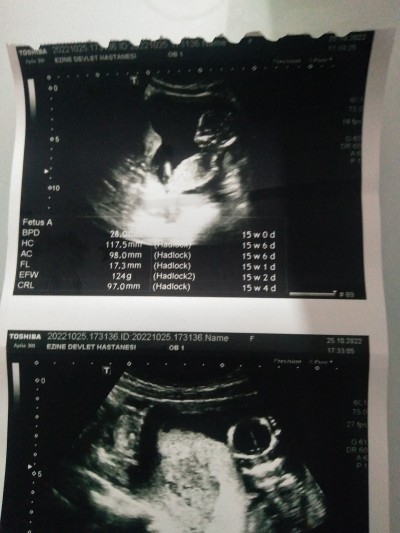

Hadi bakalım:)

image

Bu bebek erkek bebek icimden oyle gecti rabbim bilir bende usg bakmaya geldim burda hahah :D

Bende hep erkek hissediorm haftaya öğrenicez bakalim

Yok cnm kız.  Ne dersen de :) :) :) tabi rabbim bilir yine de. Allahım sağlıkla kucağına almak nasip eylesin inşallah ♡♡♡ bana yaz ama ogrenirsen

Tmm kızlar yazarim